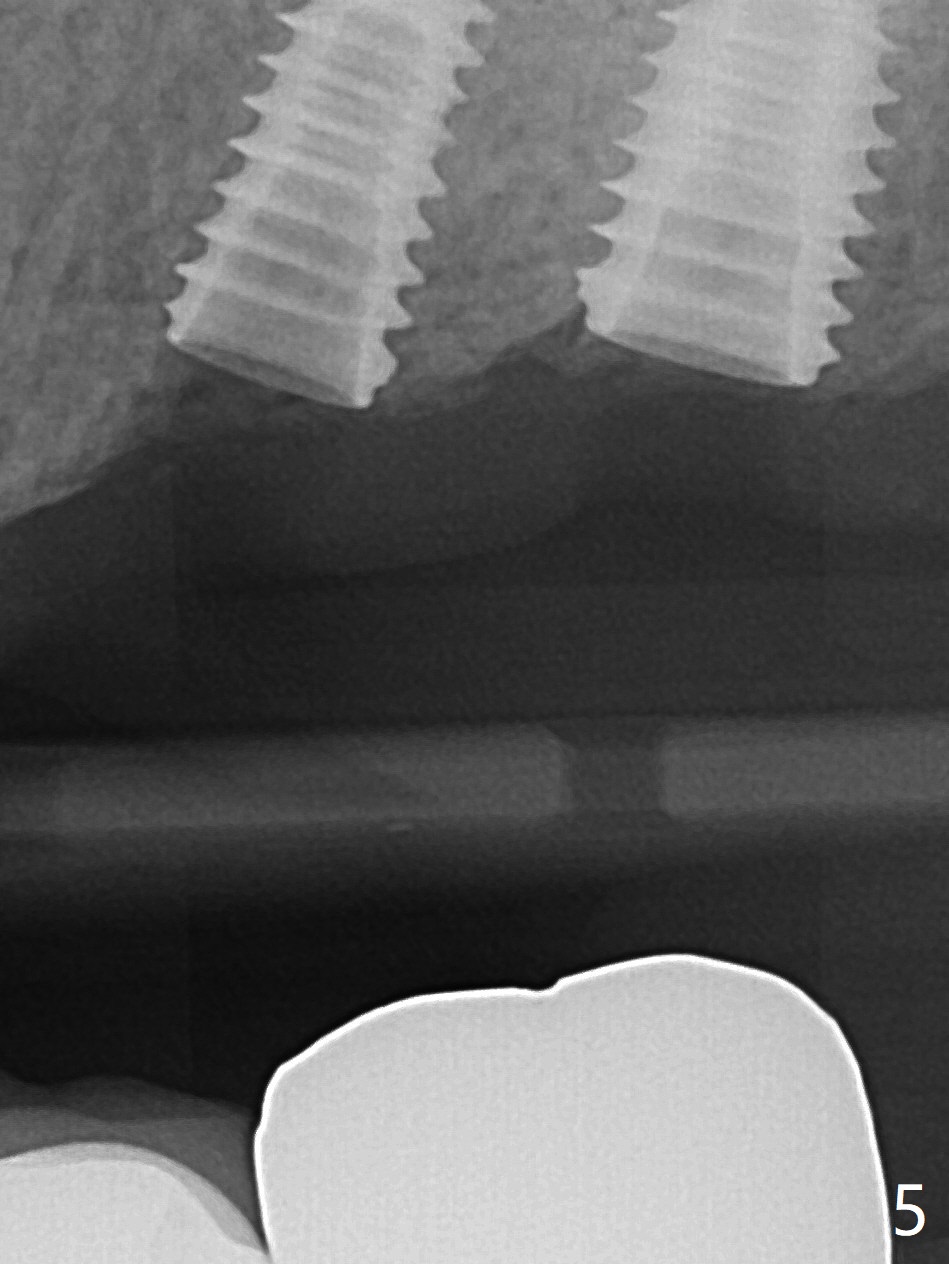

PA is taken after 2.2 mm drill reaches the depth at #13 to confirm that the osteotomy is parallel to the long axis of the tooth #12 (Fig.1). Fixture mount is used to place a 4x10 mm implant at #13 and stays as an anchor pin while osteotomy and sinus lift are being conducted at #14 (Fig.2). In fact there is discrepancy in depth using the guide. For example the last drill for osteotomy is 4.5x7.3 mm according to design, whereas 4.5x11.5 mm drill has to be used before the sinus floor has small area of perforation without sinus membrane breakage. Autogenous bone harvested from the osteotomy, PRF membrane and a 4.5x10 mm dummy implant are used for sinus lift (Fig.2). The placement depth of the implant at #13 has to be adjusted multiple times until satisfaction (Fig.2-5). The implant at #14 is infected and loosened 1.5 months postop; after its removal, the sinus floor is absent without membrane perforation; the large defect with basically intact buccal and palatal walls is grafted (Fig.6 *). Four to five months later, use the same guide and drill sequence until 3.5x7.3 mm drill. Insert a 4x10 mm dummy implant to the 2nd line of 12 mm offset and take 5x5 cm CT to determine the diameter and depth of a final implant. Use healing screw. The pattern of bone graft changes 3 months postop (Fig.7, as compared to Fig.6). Return to Upper Arch Immediate Implant, Trajectory II 矫正,糖尿病,种植水平 Xin Wei, DDS, PhD, MS 1st edition 08/06/2019, last revision 12/06/2020